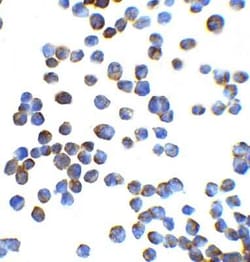

ZEB1 Polyclonal antibody specifically detects ZEB1 in Human samples. It is validated for Western Blot, ELISA, Immunohistochemistry, Immunocytochemistry/ Immunofluorescence, Immunohistochemistry (Paraffin)

| Western Blot, ELISA, Immunohistochemistry, Immunocytochemistry, Immunohistochemistry (Paraffin) | |

| Western Blot 1 μg/mL, ELISA 1:100-1:2000, Immunohistochemistry 5 μg/mL, Immunocytochemistry/ Immunofluorescence 20 μg/mL, Immunohistochemistry-Paraffin 5 μg/mL | |